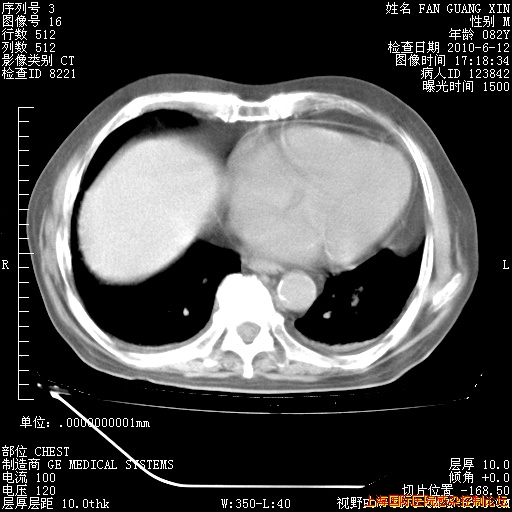

6月12日纵膈窗

今天复查CT

今天CT

整整相隔30天的肺部CT好像有所好转啊。甲强龙减量第3天,需要观察体温。

海管,自昨日你和我通完话后,不知您岳父消化道症状有无缓解?体温怎样?阅读7.12日胸部ct,个人认为目前激素治疗是有效的,甲强龙减量是适宜的。因在抗痨治疗,需密切观察肝功、肾功能和血常规。不过,老年、长期住院和大量使用激素,很担心菌群失调发生